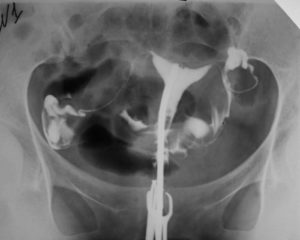

ГСГ маточных труб (гистеросальпингография) – это рентген органов малого таза у женщин с целью выявления непроходимости фаллопиевых труб и других патологий.

- Делается серия рентгеновских снимков.

Гистеросальпингография (ГСГ или рентген области маточных труб и матки) считается методом диагностики, который дает возможность рассмотреть внутренние очертания матки, а так же маточные трубы. Эта процедура так же носит название метросальпингографии.

Радиологическое обследование, в процессе которого специалист делает ряд рентгеновских снимков, считается классической гистеросальпингографией.

Метросальпингография (сокр. МСГ) представляет собой разновидность рентгенологического исследования, при котором применяется метод искусственного контрастирования. Это дает возможность понять в дальнейшем, в каком состоянии находятся фаллопиевы трубы и полость матки.

ГСГ – это диагностическая процедура, которая часто применяется в гинекологической практике. Суть ее проведения состоит в том, что специалист вводит вовнутрь матки специальное контрастное вещество. После заполнения матки и фаллопиевых труб он делает снимок с помощью рентгенологического аппарата или ультразвукового оборудования.